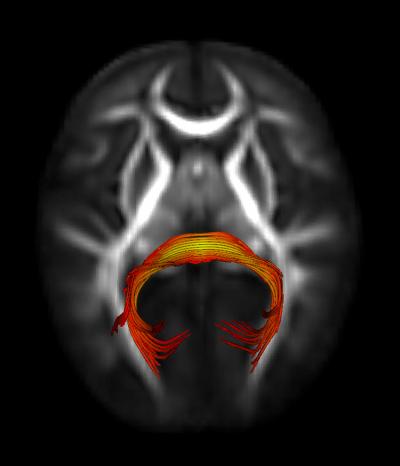

Splenium of the Corpus Callosum

image: Splenium of the Corpus Callosum: This is a white matter fiber bundle that supports visual orienting in typically developing infants and may be implicated in the early development of autism spectrum disorders. view more

Credit: Jason Wolff, Ph.D., UNC

"These findings suggest that 7-month-olds who go on to develop autism show subtle, yet overt, behavioral differences prior to the emergence of the disorder. They also implicate a specific neural circuit, the splenium of the corpus callosum, which may not be functioning as it does in typically developing infants, who show more rapid orienting to visual stimuli," said Jed T. Elison, PhD, first author of the study.

The results showed that the high-risk infants later found to have ASD were slower to orient or shift their gaze (by approximately 50 miliseconds) than both high-risk-negative and low-risk infants. In addition, visual orienting ability in low-risk infants was uniquely associated with a specific neural circuit in the brain: the splenium of the corpus callosum. This association was not found in infants later classified with ASD.

The study concluded that atypical visual orienting is an early feature of later emerging ASD and is associated with a deficit in a specific neural circuit in the brain.